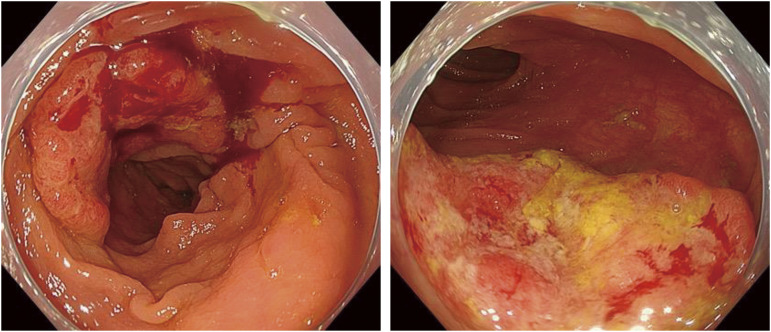

Case presentation: An 83-year-old woman was diagnosed as having advanced colorectal cancer in the transverse colon by lower gastrointestinal endoscopy, and biopsy results revealed moderately differentiated adenocarcinoma. Contrast-enhanced computed tomography showed a tumor located near the hepatic flexure and an enlarged lymph node near the tumor. No distant metastasis was observed, and the preoperative diagnosis was cT3N1aM0 cStage IIIb cancer. Immunohistochemical analysis of the biopsy specimen suggested deficient mismatch repair. During the wait for surgery, the patient was urgently hospitalized due to severe dehydration. After her general condition improved, 38 days after the biopsy, we performed laparoscopic resection of the partial ascending and transverse colon with D3 lymph node dissection. The tumor noted preoperatively was not present in the specimen, and intraoperative endoscopy revealed no tumor on the anorectal side. Additional ileocecal resection was performed, but no tumor was found in the specimen, and another intraoperative endoscopy was performed, which revealed a discolored scar near the anal margin. We determined that tumor loss or morphological change had occurred, so after additional resection of the same area, ultimately, an extended right hemicolectomy was performed. Histopathological diagnosis was pT0N0M0 pStage0 cancer with no residual tumor. The patient has progressed without recurrence at 1 year after the operation.